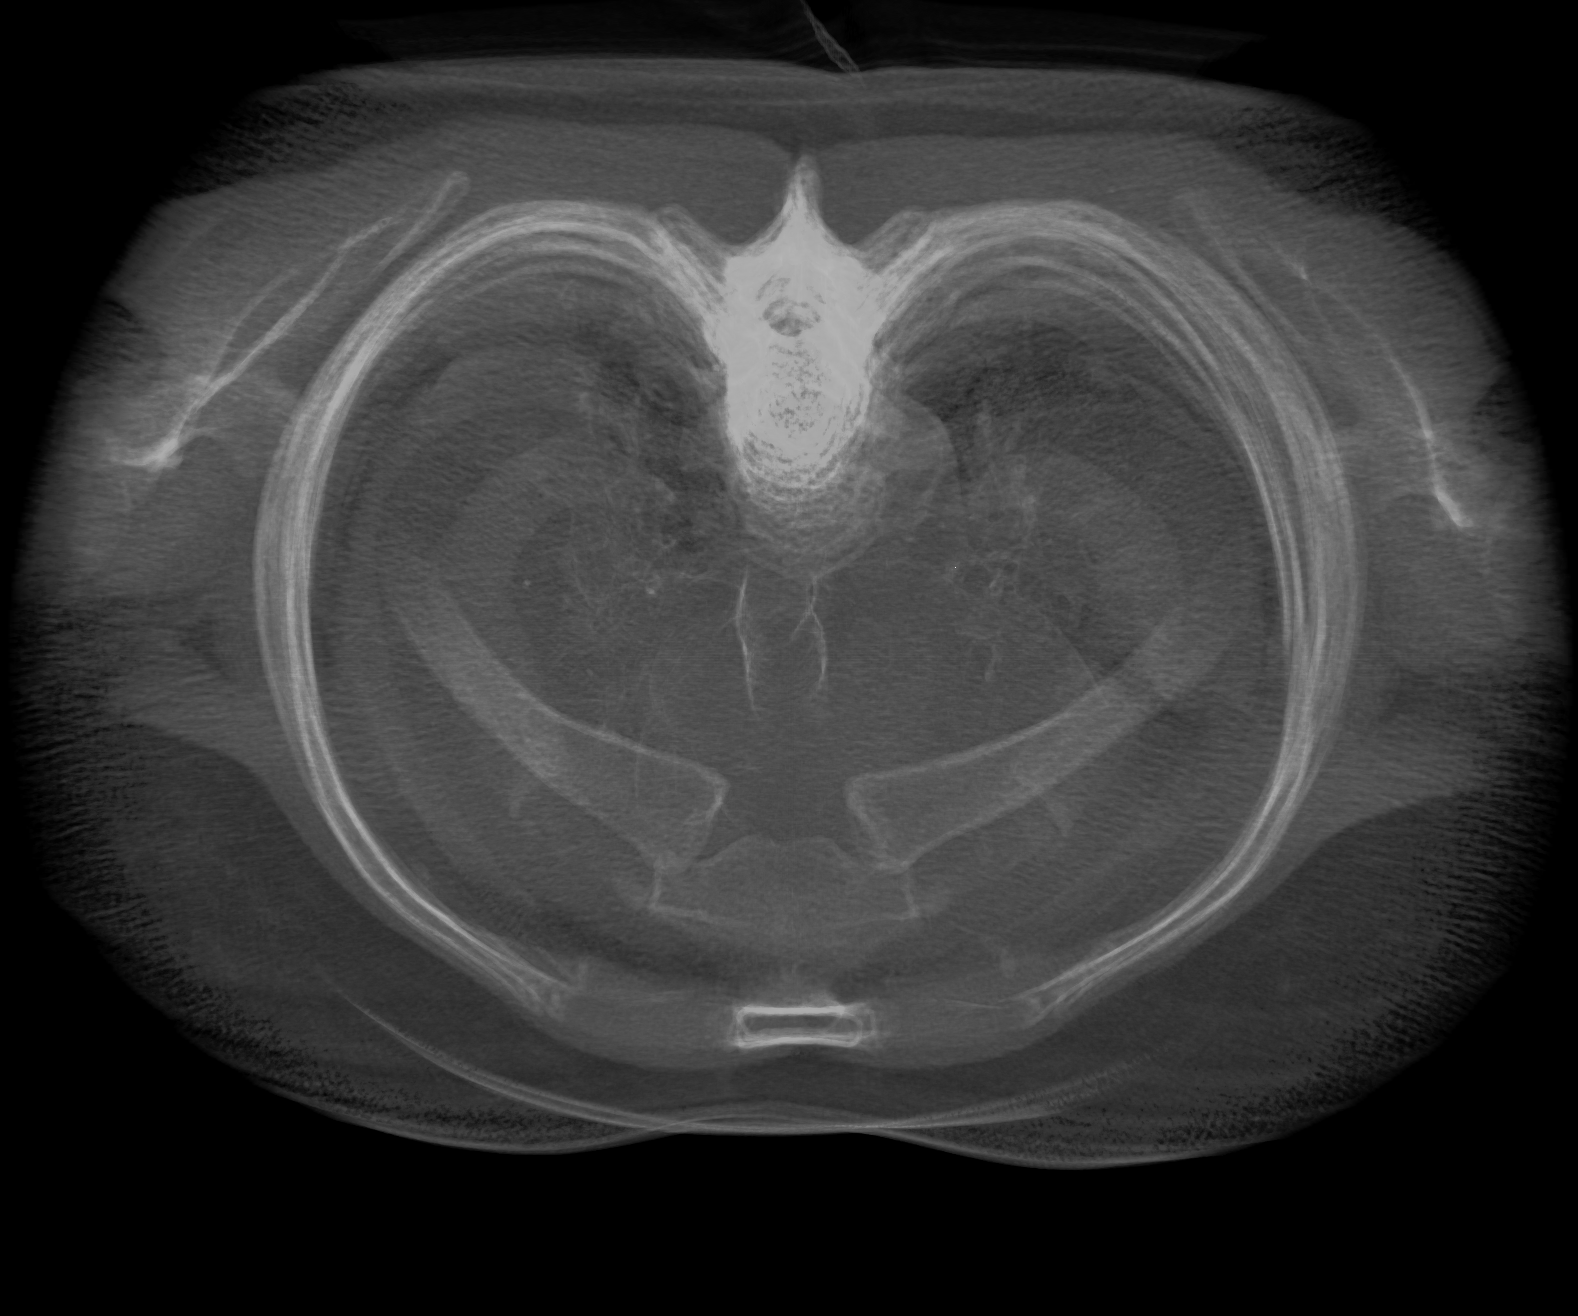

step1-16bit-fb-tex.png (973.7 KB ) - added by Tom Goddard 7 years ago.

Step 1, 16-bit framebuffer and texture.

Attachment: step1-16bit-fb-tex.png added

I attached 6 example images of a lung CT scan (folder 4-24533), grid size 512 x 512 x 236, 3d projection rendered with plane spacing minimum along 3 axes, voxel size .576 x .576 x 1.25, so about 500 planes, view along z axis, perspective projection. Step 1 and 2 look quite different with normal 8-bit rendering, but look nearly the same with 16-bit rendering. Both 16-bit framebuffer and 16-bit color/alpha texture contribute have significant effect on the appearance.